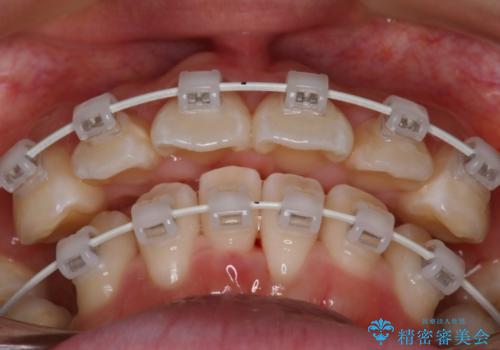

- 矯正装置

- 審美装置